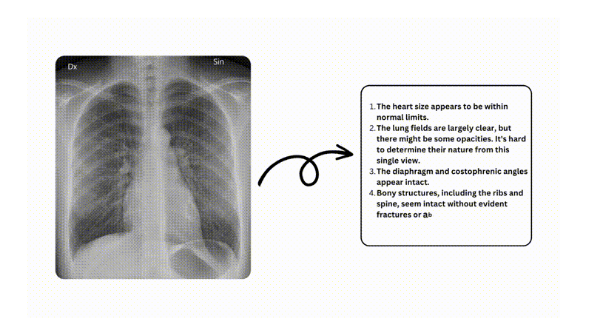

AI가 생성한 해석받기

이미지를 업로드한 후 '제출' 버튼을 클릭하세요. AI 시스템이 몇 분 안에 판독 결과를 생성하고, 엑스레이 이미지 판독이 포함된 자세한 보고서를 받게 됩니다.

보고서 검토 및 저장

AI가 생성한 판독 결과를 받으면 꼼꼼히 검토할 수 있습니다. 보고서를 기기에 저장하거나 인쇄하여 기록으로 남길 수 있는 옵션이 있어 나중에 참조하거나 상담할 때 편리하게 사용할 수 있습니다.